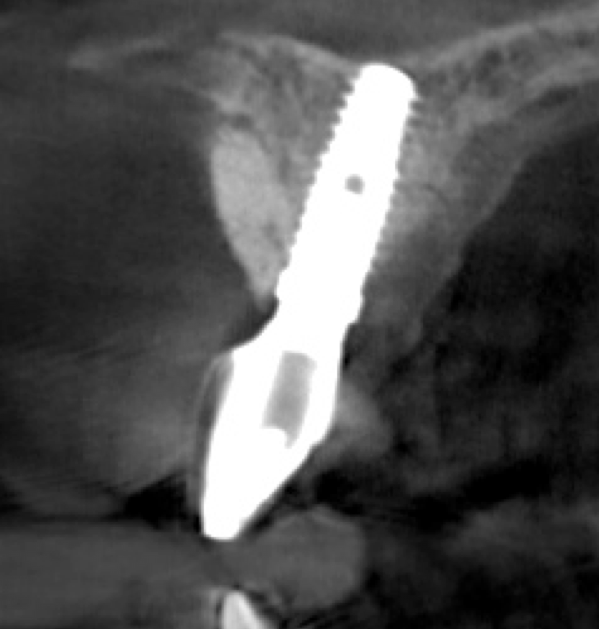

Tomographic images revealed a large tridimensional defect, with vertical and horizontal loss of bone extending to the apical third of teeth Nos. 6 and 8. Additionally, a buccal bone dehiscence was evident on tooth No. 5, and thin labial plates secondary to the orthodontic movement were present in several areas (Figure 3 and Figure 4).

Fig 4. Tomographic images revealed a tridimensional defect extending to the apical third of teeth Nos. 6 and 8, a buccal bone dehiscence on tooth No. 5, and associated thin labial plates.

Figure 4

Fig 10. Tomographic images of teeth Nos. 6 (Fig 10), 7 (Fig 11), and 8 (Fig 12) clearly showed vertical gains in alveolar height, including in the edentulous area corresponding to tooth No. 7. The apex of tooth No. 8 was located within the soft tissue because it was force-erupted beyond its socket.

Fig 12. Tomographic images of teeth Nos. 6 (Fig 10), 7 (Fig 11), and 8 (Fig 12) clearly showed vertical gains in alveolar height, including in the edentulous area corresponding to tooth No. 7. The apex of tooth No. 8 was located within the soft tissue because it was force-erupted beyond its socket.

Figure 12